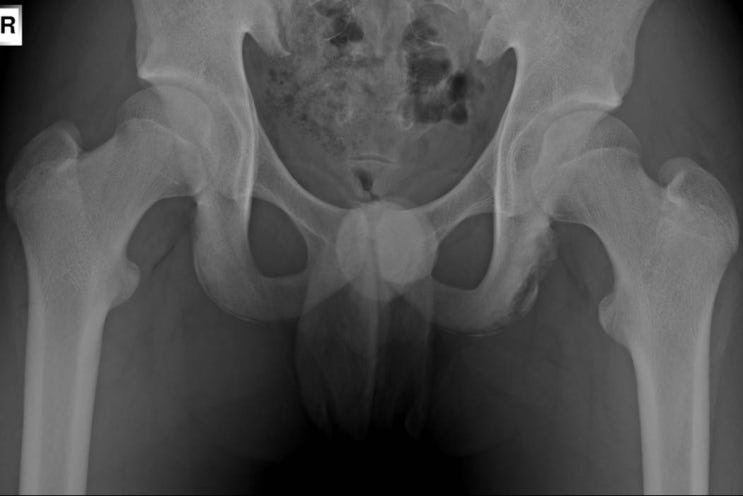

[골반][증례] ischial tuberosity Avulsion fracture or apophysitis (소아 성장판 견연 골절)

[7271] M/13 다리찢기와 태권도 선수 r/o ischial tuberosity apophysitis or avulsion fx 오래전부터 엉...